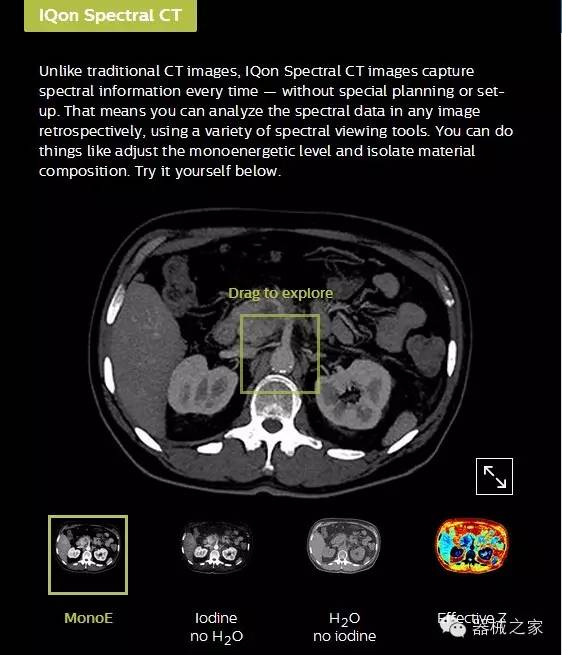

IQon光譜CT能夠按照需求提供光譜量化和工具,并能通過簡單工作流程、在低劑量下對(duì)結(jié)構(gòu)進(jìn)行定性分析

IQon光譜CT -- 是業(yè)界首臺(tái)以探測器為成像基礎(chǔ)的光譜CT,它可以在單次常規(guī)掃描下獲得傳統(tǒng)解剖影像及光譜功能影像。不僅可以提供精準(zhǔn)的診斷信息,還可簡化工作流程、在低劑量下完成定量與定性分析。